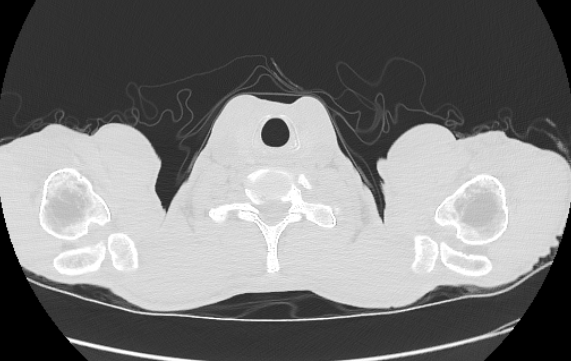

CT Lung

CT Lung CTA

CT Abdomen

CT Abdomen MRI Spine